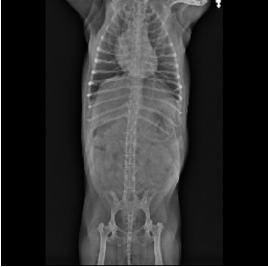

의뢰영상

* 복부팽만, Back pain, Left TL limb knuckling, Lethargy, anorexia로 내원한 환자로 흉,복부 4장으로 판독하였음.

- 복부팽만, back pain, left TL limb knuckling, lethargy, anorexia로 내원한 환자로 흉,복부 4장으로 판독하였음. Technical consideration) 흉, 복부 촬영 시 Field of view를 흉부/복부로 나누어 촬영하여야 하며, 기본적으로 일반 흉부 사진의 경우 VD view, Rt. Lateral view, Lt. Lateral view가 촬영되어야 하며, 종양, 심질환 등이 의심된다면 DV view 추가 촬영이, Tracheal collapse, bronchomalacia와 같은 호흡기계 질환이 의심된다면 DV view 흡/호기, Lt. lateral view 흡/호기 추가 촬영이 필요함. 흉부 촬영 시 양측 rib이 일치되어 하나로 보이게 촬영하여야 함. 척추 방사선 촬영 시 vertebra의 endplate가 일치되어 하나의 선으로 보이게 촬영하여야 함. 방사선 촬영 시 환자가 움직여 blur하게 촬영되었다면 추가 촬영을 진행하여야 함. 방사선 상 보정자의 손이 촬영되지 않게 주의하여 촬영해야 함. Thorax) 기관 및 lower airway 주행의 이상소견은 관찰되지 않음. VHS는 10.2로 정상범위 내로 측정되며 특정 chamber의 dilation은 관찰되지 않음. 폐 실질, 폐 혈관의 이상소견은 관찰되지 않음. Abdomen) 복강 내 serosal detail은 정상적으로 관찰됨. 간은 rib cage를 moder ate to severe한 정도로 enlarged되어 벗어나 위치하며 margin은 sharp하게 관찰됨. 양측 신장은 복강 장기와의 summation으로 인해 명확한 평가의 한계가 존재하나 다소 정상적인 shape, margin으로 판단되며 다소 후방변위되어 관찰됨. 방광 후방에서 기시하여 방광 전방으로 주행하는 undulant한 관상의 구조물이 관찰됨. Spine) 좌전지의 평가를 위해서는 최소 경추 방사선 사진과 앞다리 사진이 필수적임. 이러한 사진없이 판독은 불가함. C spine intervertebral disc space는 정상적으로 후방으로 갈수록 다소 넓어지는 양상이 아니며, 주관적으로 다소 좁아져 관찰되나 이 사진으로는 평가 의미부여가 어려움. C2-C4 vertebra ventral endplate의 spondylosis deformans가 관찰됨. T12-T13, T13-L1 disc space는 mild한 정도로 narrowing되어 관찰됨. L1-L5 disc space 및 intervertebral foramen은 moderate한 정도로 narrowing되어 관찰되며 mild한 spondylosis deformans를 동반하고 있고 L2-L3 disc는 mineralization되어 관찰됨.

- Impressions

- 복부 팽만, back pain, lethargy, anorexia로 내원한 환자로 복부 방사선 검사 상 자궁으로 의심되는 구조물이 관찰되며, 환자의 연령 및 품종 소인을 고려 시 pyometra, hydrometra, mucometra의 가능성이 likely할것으로 판단되며, 복부 초음파 검사를 통한 해당 구조물의 명확한 평가가 추천되며, 환자의 임상증상 또한 이에 기인하였을 가능성이 존재하므로 즉각적인 검사 및 clinical indication이 될 경우 빠른 수술적 교정이 추천됨. moderate to severe한 hepatomegaly가 관찰되며, 간 margin이 다소 sharp하며, generalized한 hapatomegaly를 보이는 점 및 환자의 연령을 고려 시 Cushing, Diabetes mellitus, Steroid induced hepatomegaly의 가능성이 우선 고려되며 다소 정상적인 Caudal vena cava를 고려 시 venous congestion의 가능성은 less likely할것으로 판단됨. 해당 질환의 명확한 감별을 위한 복부초음파 스크리닝 검사가 우선 추천되며 Clinical indication이 될 경우 호르몬 검사, 뇨검사 등이 추천됨. TL spine multifocal한 영역의 disc space, intervertebral foramen narrowing 및 C spine disc space의 주관적인 narrowing이 관찰되며 환자의 back pain임상증상, Lt TL knuckling, 환자의 연령이 다소 노령인 점을 고려 시 C spine, TL spine Intervertebral disc disease의 가능성이 우선고려 되며 유사한 임상증상을 나타낼 수 있는 다양한 척수 질환에 대한 감별을 위해 MRI촬영이 추천될 수 있습니다. 해당 질환의 경우 progressive한 양상으로 진행되는 경우가 많으며 현재 다른 임상증상 없이 back pain만 관찰되는 경우라면 단기간의 NSAIDs처방, Cage rest 등의 대증적인 치료를 진행해 볼 수 있으나 임상증상의 악화, deep pain 소실 등의 증상이 나타난다면 MRI촬영 및 검사 결과에 준한 수술적 치료 또한 지시될 수 있습니다.

- Recommendation

- - 복부 초음파 검사를 통한 자궁 평가

- - clinical indication이 될 경우 경추, 흉요추 MRI 검사